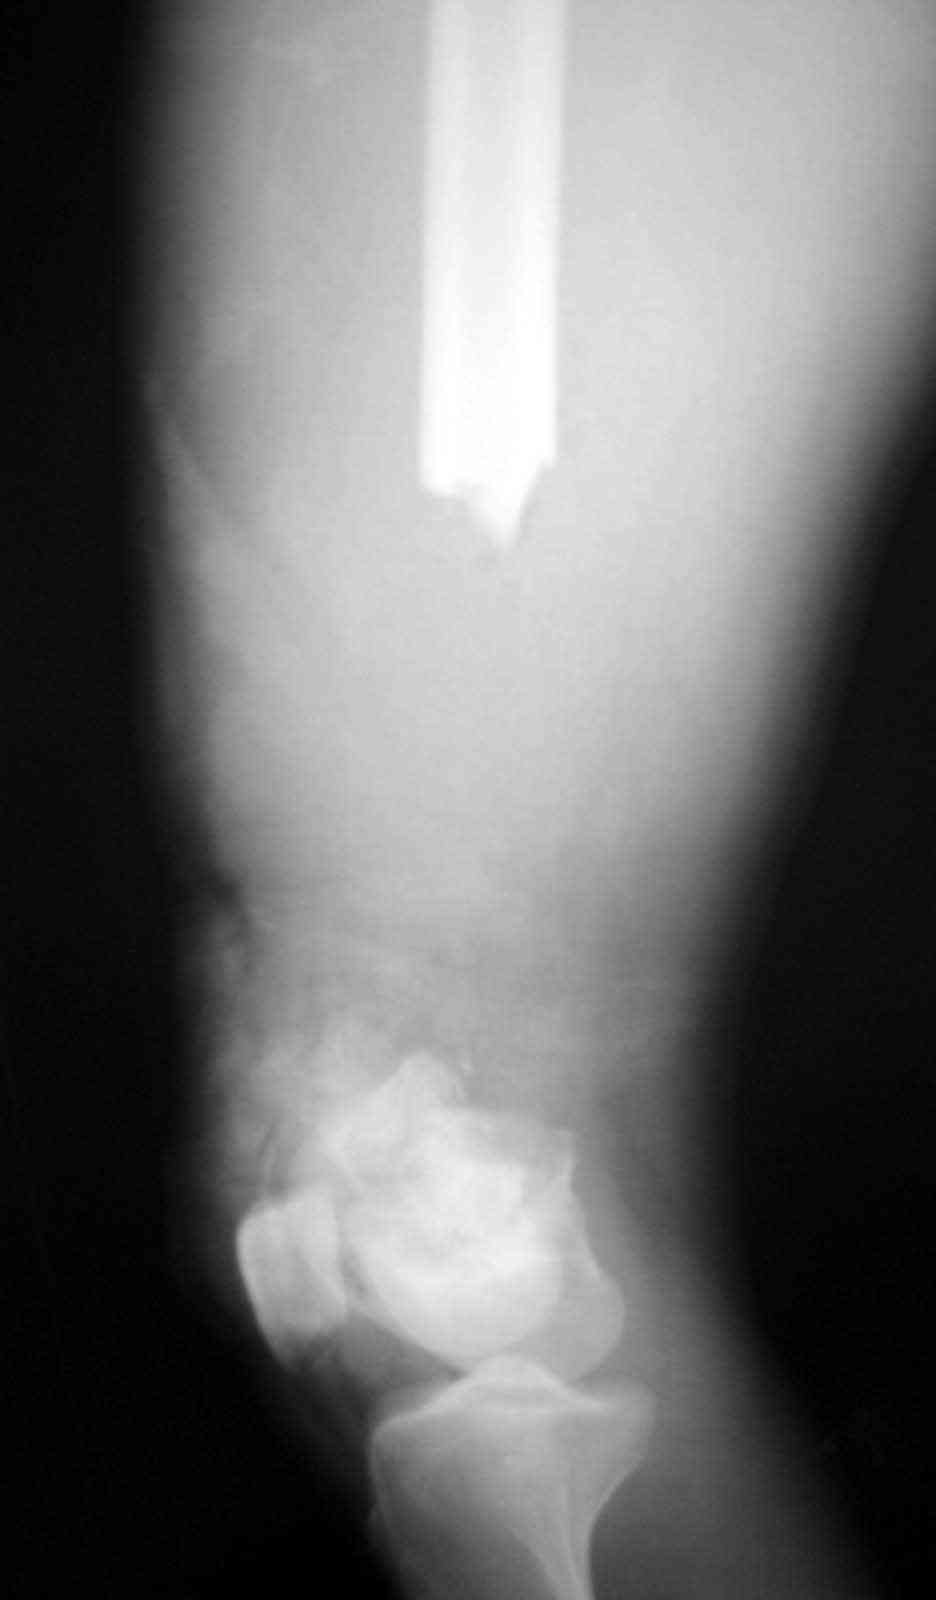

dear MAGDY we have treated exactly similar case intially with debridement & ILIZAROV ring fixator by end of three months patient had exuberent callus along whole length of left out periosteal sleeve &fixator was removed walking spica was applied, unfortunately after one month in spica he developed break in the bridging bone and now we have treated him with locking plate &bone graft one month back and on CPM machine with knee movement of 90 deg.